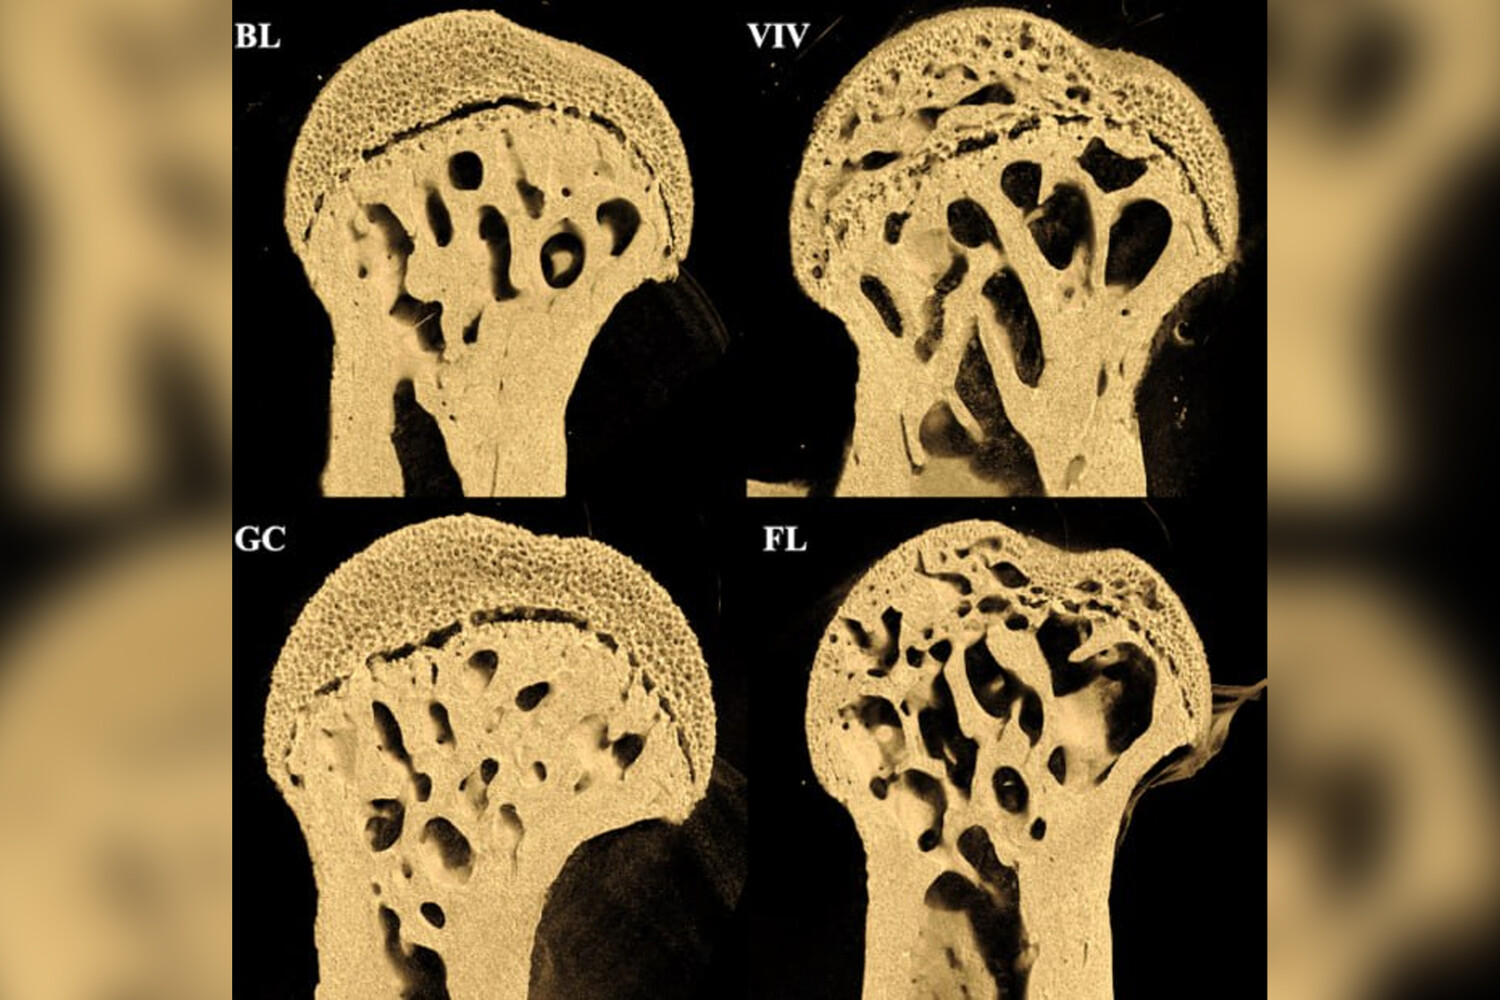

Эксперимент продолжительностью 37 дней показал, что у мышей в космосе значительно пострадали бедренные кости, в то время как поясничный отдел позвоночника остался практически неповрежденным.

Особенно заметные повреждения — крупные отверстия — обнаружились на концах бедренных костей в местах соединения с тазобедренным и коленным суставами.

Исследование опровергло предположение о том, что основную роль в потере костной массы играет космическая радиация. Как выяснилось, повреждения костей развиваются по другому механизму — изнутри наружу, что не характерно для радиационного воздействия.